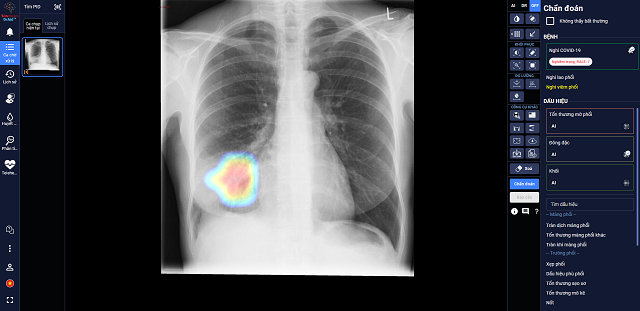

DrAid cho COVID-19 - sản phẩm ứng dụng Trí tuệ nhân tạo (AI) của Công ty Cổ phần VinBrain (thuộc Tập đoàn Vingroup) – vừa được Hội đồng Khoa học Bộ Y tế nghiệm thu và đặc biệt kiến nghị nên sớm đưa vào sử dụng hàng ngày tại các bệnh viện trong giai đoạn COVID-19 đang tiếp tục lây lan như hiện nay. Đây được coi là một công cụ hỗ trợ sàng lọc và tiên lượng điều trị COVID-19 mới hữu hiệu, góp phần chủ động dự phòng và kiểm soát dịch hiệu quả.